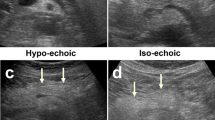

To assess the performance of computed tomography (CT) texture analysis to predict the presence of adherent perinephric fat (APF).

Seventy patients with small renal tumors treated with robot-assisted partial nephrectomy were included. Patients were divided into two groups according to the presence of APF. We extracted 15 image features from unenhanced CT and contrast-enhanced CT corresponding to first-order and second-order Haralick textural features. Predictors of APF were evaluated by univariable and multivariable analysis. Receiver operating characteristic (ROC) analysis was performed and the area under the ROC curve (AUC) to predict APF was calculated for the independent predictors.

Results from this preliminary study suggest that CT texture analysis might be a promising quantitative imaging tool that helps urologist to identify APF.